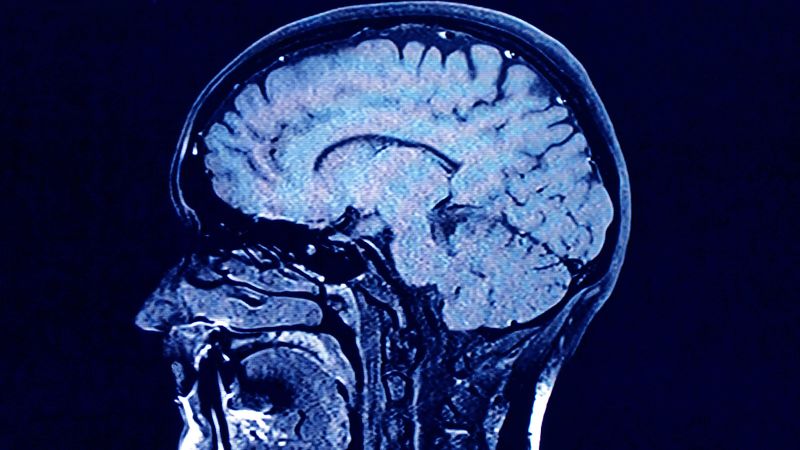

Unraveling the Mysteries of Brain Aging: Genetics, Predictions, and Lifelong Performance

The Lothian Birth Cohorts study, conducted by the University of Edinburgh, has tracked the cognitive abilities of individuals from age 11 into their 70s, 80s, and 90s, revealing that about half of our intelligence in old age is determined by childhood cognitive abilities. The study highlights the significant variation in brain aging among individuals and suggests that while genetic factors and childhood intelligence play roles, lifestyle choices like physical activity and education also influence cognitive aging. The research underscores the importance of multiple small lifestyle changes to promote healthier brain aging.